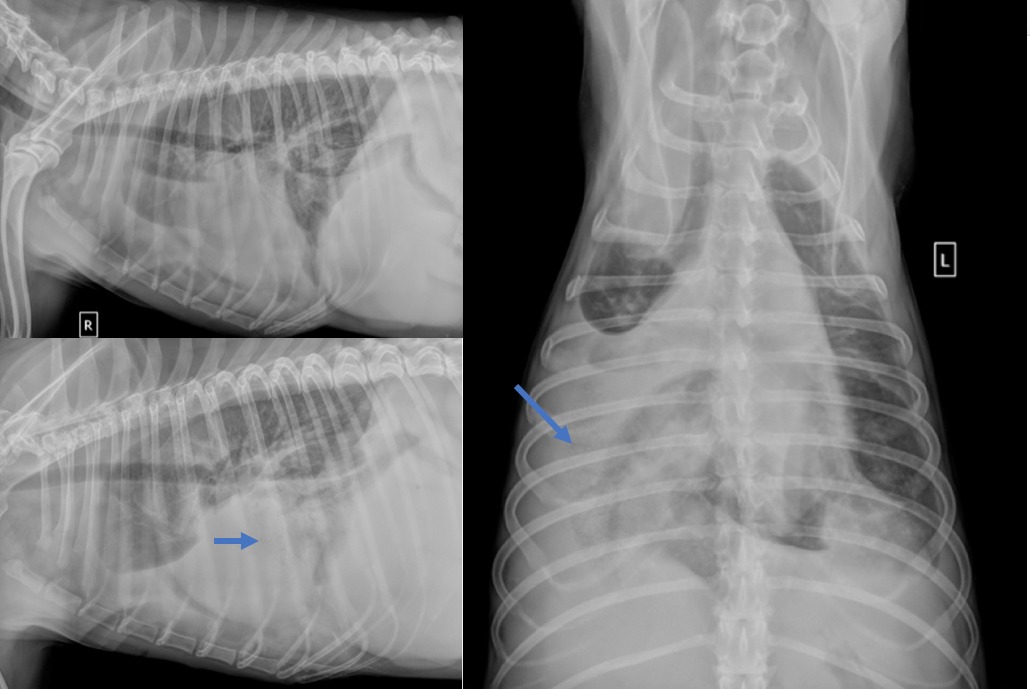

Reconnaître les types d’opacification pulmonaire

Quelles sont les opacités anormales visibles sur ces radiographies (profil latéral droit et VD) ? 1 – Opacité bronchique. 2 – Opacité interstitielle et bronchique. 3 – Opacité bronchique et alvéolaire. Si vous avez coché le choix 3, c’est la bonne réponse 😁 La méthode d’interprétation des anomalies du parenchyme pulmonaire… Lire la suite